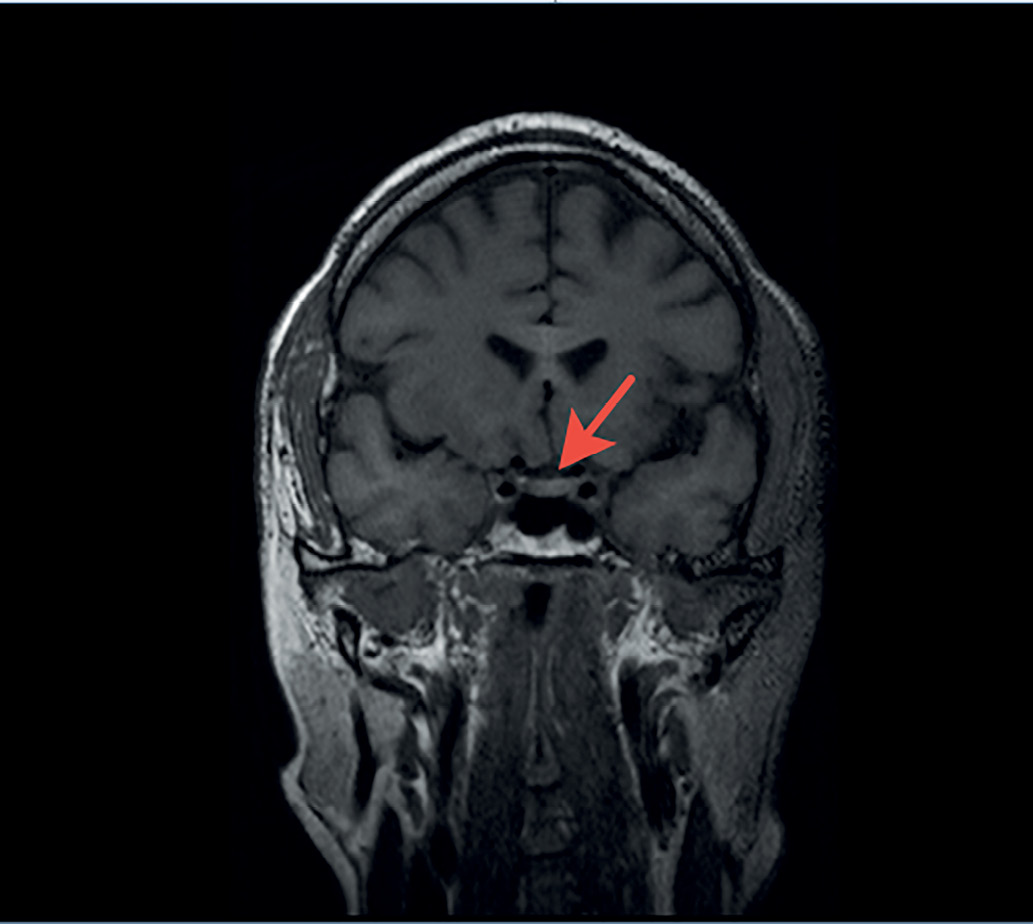

С целью визуализации хиазмально-селлярной области пациенту выполнена магнитно-резонансная томография (МРТ), которая не выявила опухолевых или воспалительных образований и аномалий развития головного мозга. Гипофиз имеет нормальные размеры: вертикальный — 5 мм, поперечный — 13 мм, переднезадний — 9,1 мм. Структура аденогипофиза однородная, воронка расположена по средней линии (рис. 1, 2). Отмечено отсутствие типичного сигнала от задней доли гипофиза,а проведение контрастного усиления не выявило каких-либо дополнительных изменений гипоталамо-гипофизарной области, в связи с чем диагноз идиопатического ЦНД у пациента был подтвержден.

Рисунок 1. МР-картина хиазмально-селлярной области пациента. Фронтальный срез.

Figure 1. MRI of the patient's chiasmal-sellar area. Front cut.

Рисунок 2. МР-картина хиазмально-селлярной области пациента. Сагиттальный срез.

Figure 2. MRI of the patient's chiasmal-sellar area. Sagittal section.

Важным параметром МРТ, высокоспецифичным для ЦНД, является снижение характерного свечения от нейрогипофиза на Т1-взвешенных изображениях. Гиперинтенсивность задней доли, наблюдаемая в норме, происходит от наличия секреторных гранул, богатых фосфолипидами, в которых содержится АДГ. При нарушении синтеза и секреции АДГ, а также в ситуациях его повышенных трат (например, декомпенсированный сахарный диабет) такой сигнал пропадает и обе доли имеют одинаковую интенсивность. Таким образом, отсутствие характерного сигнала от нейрогипофиза по данным МРТ головного мозга у представляемого нами пациента дополнительно свидетельствовало о наличии ЦНД.